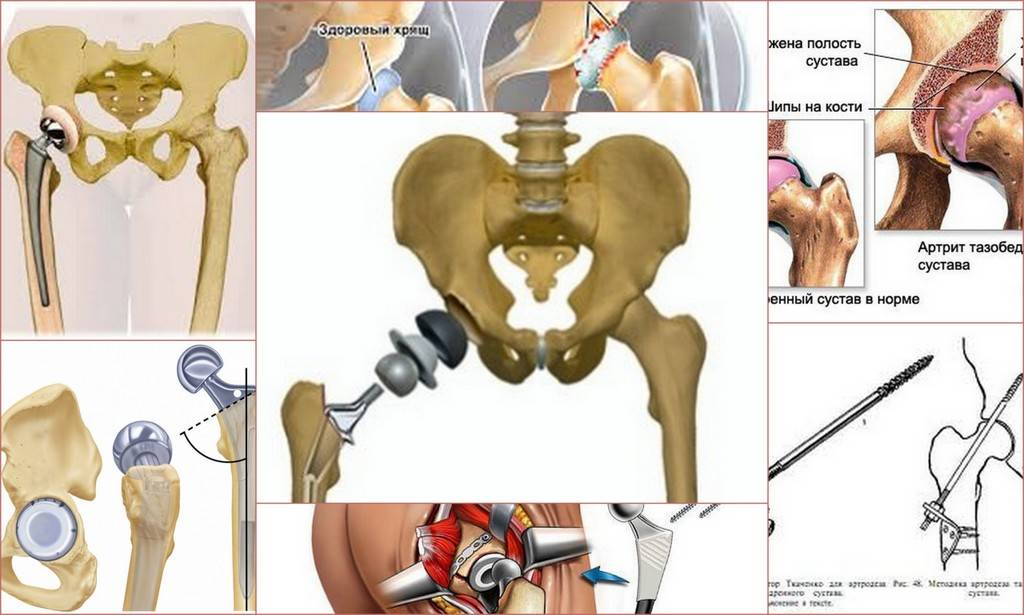

Замена таз сустава

Замена таз сустава 113 фотографий